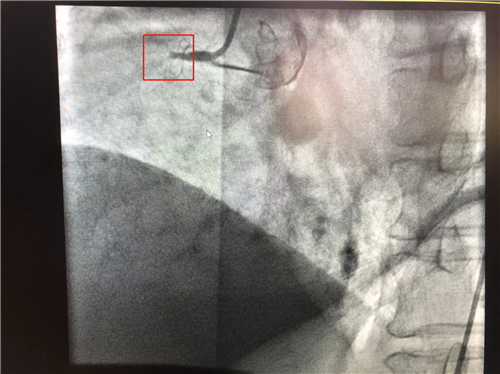

時間就是心肌,時間就是生命。導(dǎo)管室內(nèi),心血管內(nèi)科副主任徐先進(jìn)、主任助理農(nóng)彥林已然待命,病人一到,團(tuán)隊立即為其行深靜脈穿刺泵入血管活性藥物等,情況緩解后,行多體位冠狀動脈造影,確認(rèn)RCA(右冠狀動脈)近端完全閉塞。經(jīng)家屬同意,在汪念東院長的指導(dǎo)下,徐先進(jìn)、農(nóng)彥林、張星為患者行經(jīng)皮冠狀動脈球囊擴張成形術(shù)+經(jīng)外周靜脈穿刺中心靜脈置管術(shù)。術(shù)中,張奶奶再次出現(xiàn)室顫,心血管內(nèi)科團(tuán)隊臨危不亂,立即予以300焦電除顫搶救,患者竇性心律恢復(fù)。隨后,球囊擴張為其置入心臟支架,復(fù)查造影顯示血管恢復(fù)暢通,無明顯夾層,殘余狹窄不到10%。術(shù)后,張奶奶血壓偏低,轉(zhuǎn)入ICU無創(chuàng)呼吸監(jiān)護(hù),2天后轉(zhuǎn)回心血管內(nèi)科護(hù)理。

術(shù)前:右冠近端閉塞